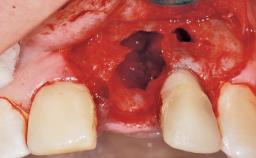

A 33-year-old female patient presented with an upper left central incisor that required extraction after a failed endodontic therapy. The tooth had been traumatized when the patient was a teenager and had undergone several endodontic treatments, including two apicectomy procedures. The patient was in good health and did not smoke. Clinical examination showed that the patient had a high lip line. In full smile, the gingival margins of the upper teeth were visible to the first molars. The gingival margins of central incisors 11 and 21 were only just showing. Examination of tooth 21 confirmed that the tooth was mobile and had hypererupted by 1 mm.

| Socket Integrity | Damage to one or more bone walls |

| Bone Volume | Damage to one or more socket walls |